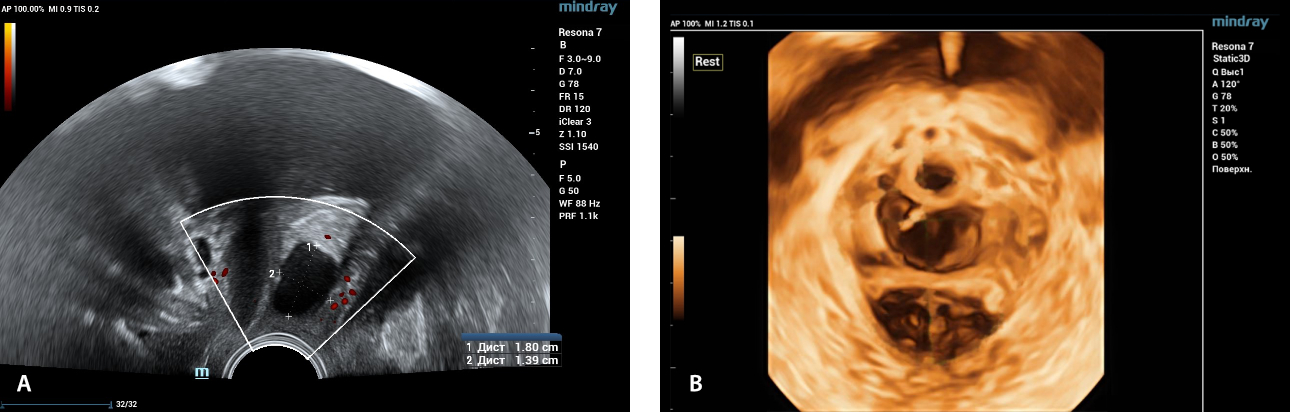

형상 1. 2D 도플러검사 와 초음파(echograms) (A), 환자 D의 휴식 상태에서 경질 접근(transvaginal access)에 의한 골반 바닥의 3D 재구성 (B)., 질 전벽(anterior vaginal wall)의 자궁내막양 낭종(endometrioid cyst)이 있는 26세 환자.

내강 용적 컨벡스 트랜스듀서(Endocavity volume convex array transducer)(DE10-3WU, Resona 7, 마인드레이)를 사용한 초음파 진단중, 요도의 중간 1/3 따라 질 전벽(anterior vaginal wall)의 투영에서 18x14 mm 크기의 난형 형태(an ovoid-shaped formation) with a parietal fine suspension, 트랜스듀서 견인에 변위되지 않음(non-displaced), 민감하며,  CDI 모드의 단일 혈관 위치들이 시각화되었습니다. 3D 재구성 -  고에코 성 격막(hyperechoic septa)이 있는 이질적인 내용을 가진 형성.